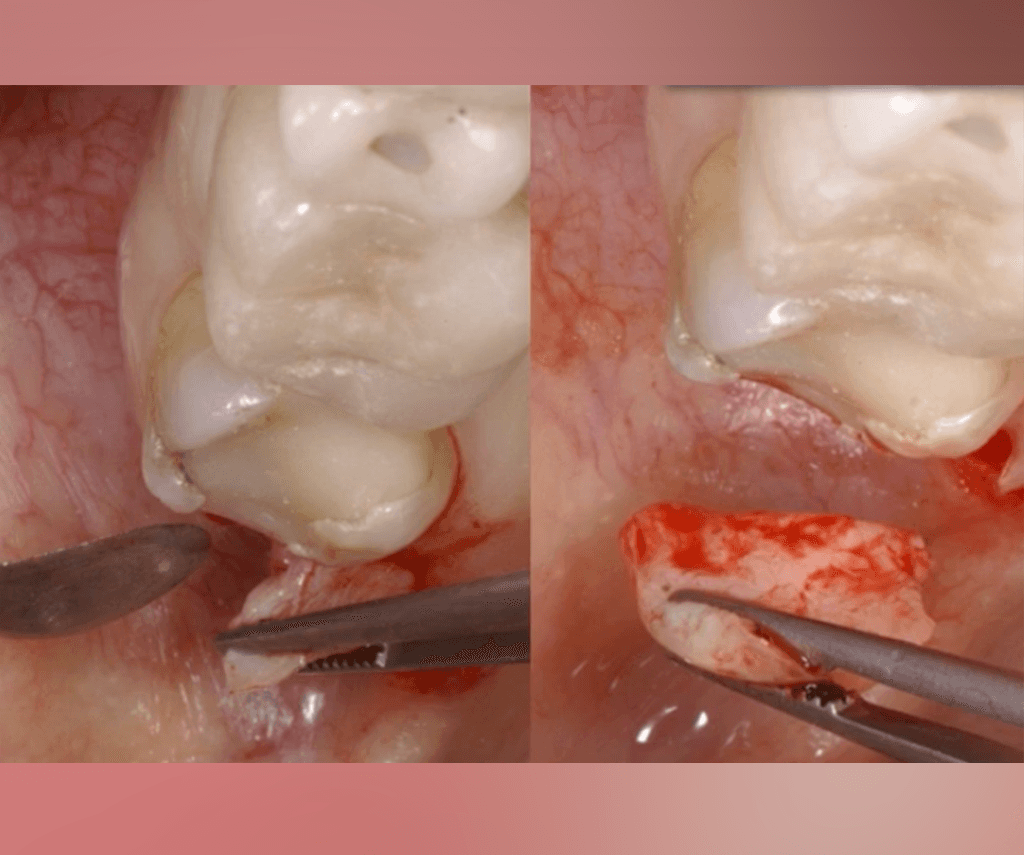

Inside Partial Extraction Therapy by CIDN

Learn how to Manage Complications

Assess various PET cases